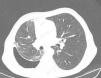

Chest Computed TomographyAs previously mentioned, patients with lung entrapment or trapped lung present thickening of the visceral pleura. However, it is very difficult to observe on chest radiography, or even conventional CT, as the thickness is usually less than 3mm. In order to demonstrate pleural thickening, Huggins et al. suggested performing what they call CT with air contrast (Fig. 3). The technique entails creating pneumothorax during pleural manometry in those patients who meet the following criteria: appearance of PP (less than −25cmH2O) and exclusion—due to the clinical history and analysis of the pleural fluid—of malignancy or active pleural inflammation. The pneumothorax is able to determine the thickening of the visceral pleura and, in addition, allows for fluid to keep being drained, if necessary, and alleviates the chest pain generated by excessively negative pressures. The procedure consists of opening a valve in the manometer circuit in order to allow air to enter into the pleural space until physiological pleural pressures are reached (mean pleural liquid pressure −5cmH2O). This procedure can only be done with monitoring and the use of a digital manometer. Even so, the demonstration of pleural thickening, the persistence of pneumothorax in conditions of negative PP and high PEL, in the absence of other causes of unexpandable lung, establish the presence of some consistent mechanical conditions (although not diagnostic) of trapped lung.13